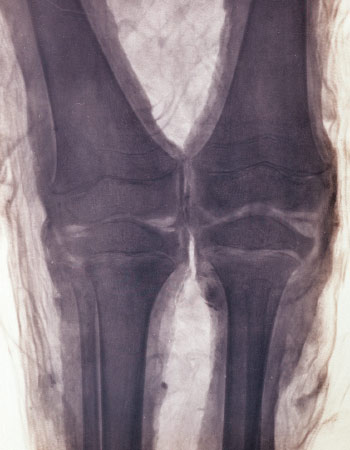

MUMMY MYSTERY Little was known about this mummified Egyptian child (top) when German physicist Walter Koenig used X-rays to look beneath its wrappings in 1896. Modern CT scans provided a more informative peek, revealing, among other findings, a completely preserved skeleton (bottom).

S. Zesch et al/Euro. J. Radiol. Open 2016